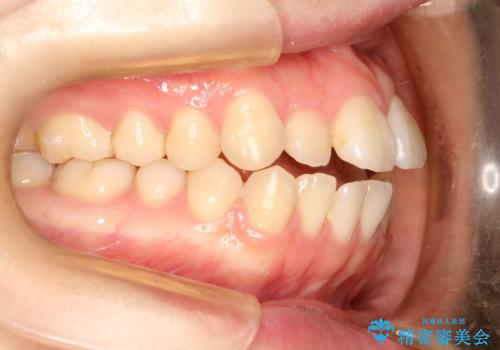

前歯がガタガタ・噛み切りにくい インビザラインによる歯を抜かない矯正

前歯にがたつきがあり、上下の歯が咬み合っていない状態でした。

歯列の横幅をひろげるのと、歯と歯の間をわずかに削ることにより、前歯のがたつきと、開咬を改善しました。